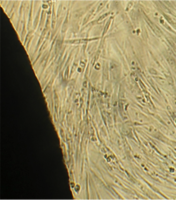

6 серия экспериментов. Образец исследуемого материала (аллогенный ГАП серии «Лиопласт»® массой 2 мг) помещали на дно культуральной чашки, после чего высевали фибробласты в стандартной концентрации.

Щелочной материал резко ухудшает прикрепление фибробластов к дну культуральных чашек (рис. 35) на всей его площади, вместе с тем прикрепившиеся клетки имеют четкие границы, нуклеолемма четко контурирует, цитоплазма гомогенная, без патологической зерностости, вакуолей и включений.

Рис. 35. Выраженная пролиферация, восстановление плотности монослоя.

Фибробласты лишь более распластаны по дну чашки, но это характерно для культуры с малой плотностью.

Вокруг образца через сутки от начала эксперимента клетки не прикрепляются (расстояние от края образца до границы 1,3±0,12 мм).

В последующие дни и до конца наблюдения плотность монослоя  в отдаленной от образца зоне нарастает даже несколько быстрее, чем в контроле, клетки сохраняют обычную для фибробластов в культуре морфологию.

Большое количество слущенных клеток в ростовой среде объясняется ухудшением прикрепления пассированных клеток, а не гибелью уже прикрепившихся (табл. 14).